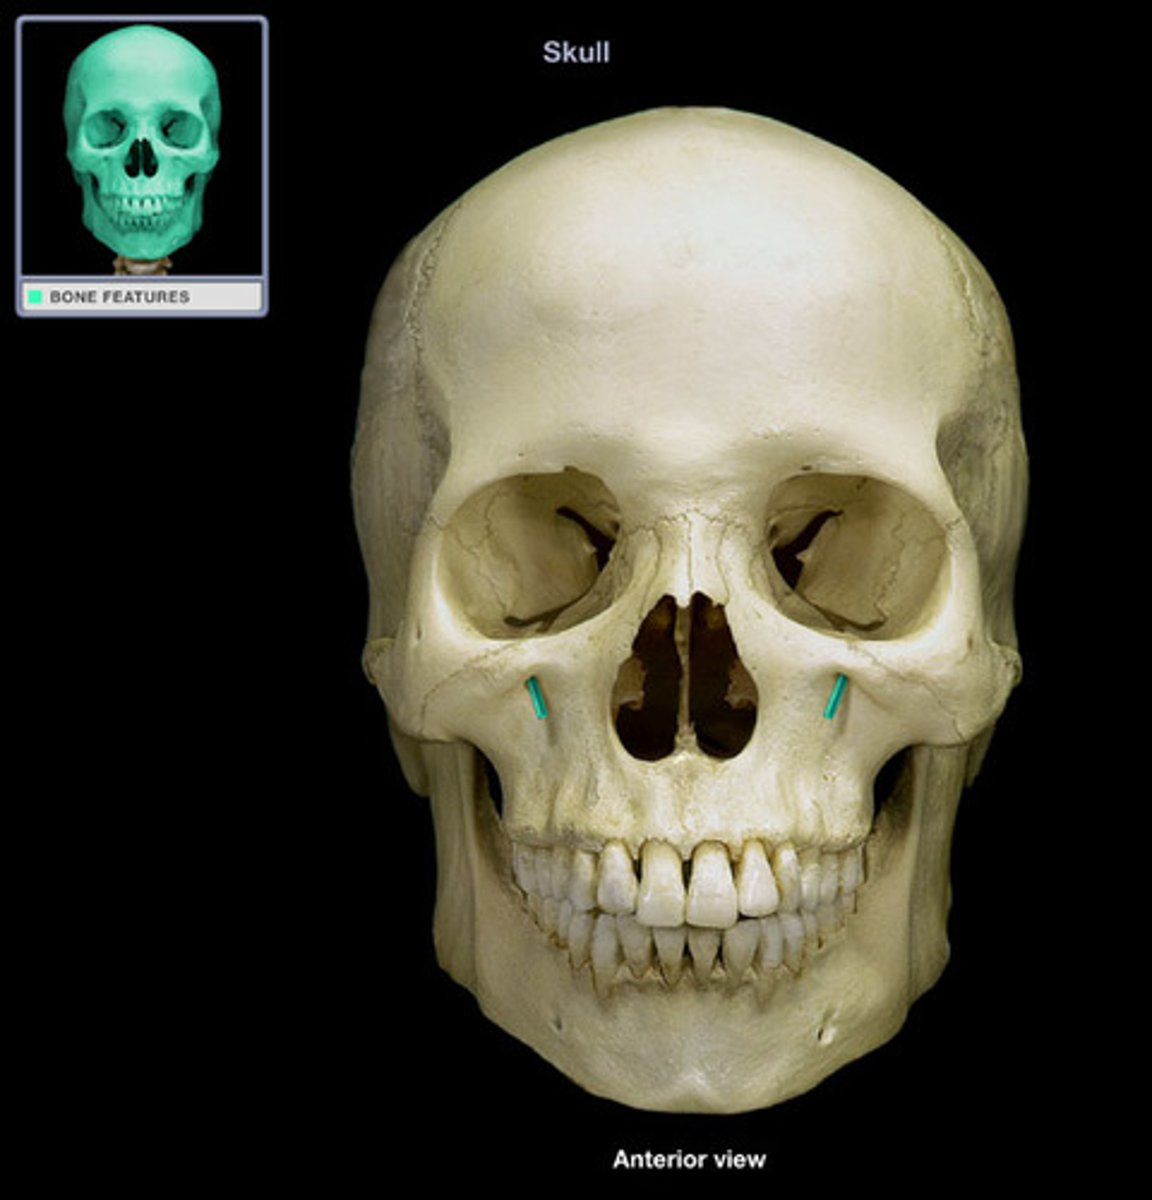

Infraorbital foramen

Mental foramen